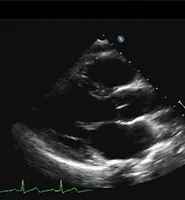

Echocardiography  (0) 2016.11.27